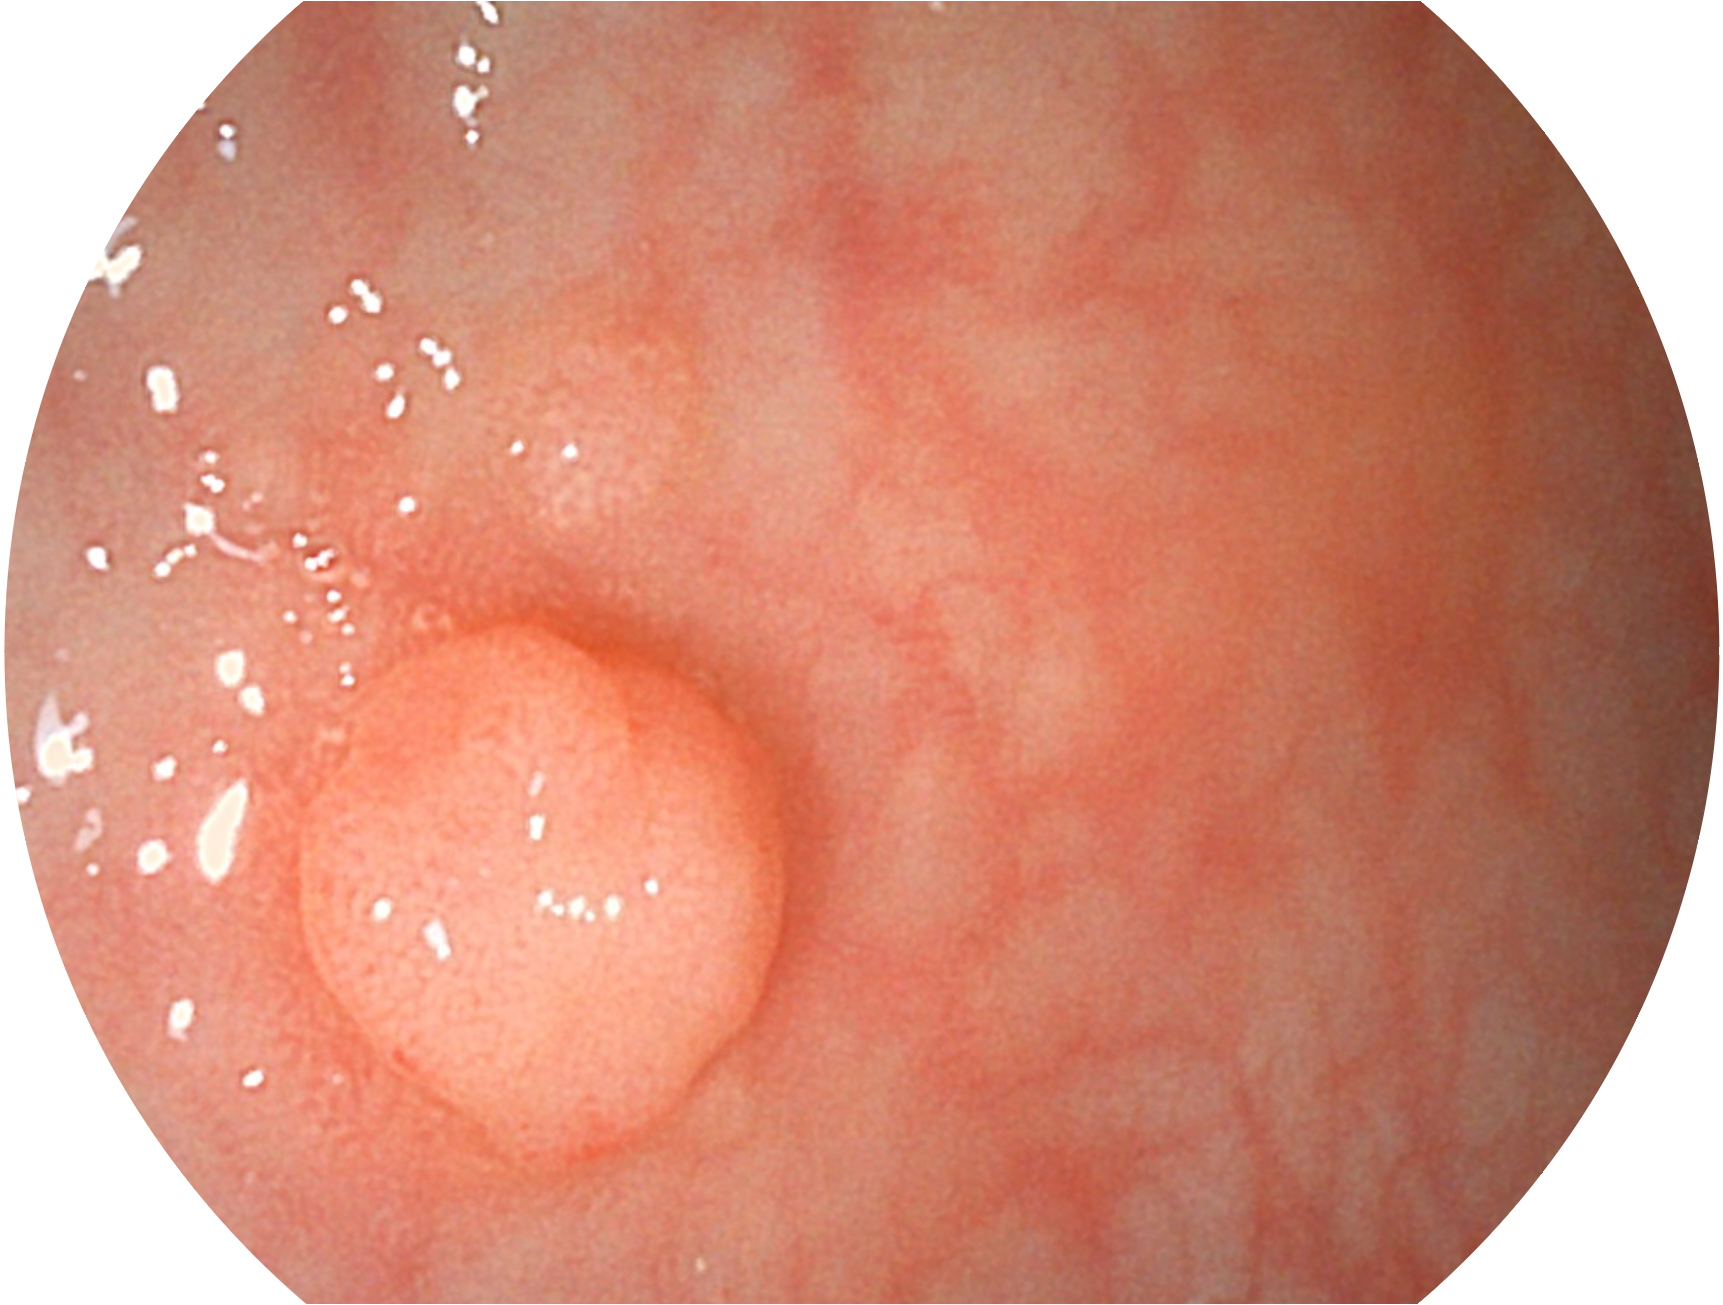

welcome海洋之神新开发的内镜染色技术,主要是基于多波长LED 光源的开发,VLS-55Q 四波长LED 光源是由四个不同颜色的LED光按照相应照明模式所规定的特定发光比例进行合束后形成,合束后形成的照明光的光谱由红光、绿光、蓝光及蓝紫光这四个不同的波段范围构成。具有更高光谱自由度,通过光谱比例的控制,实现了聚谱成像技术,英文全称为“Spectral Focused Imaging, SFI”,缩写为“SFI”和光电复合染色成像技术,英文全称为“Versatile Intelligent Staining Technology, VIST”,缩写为“VIST”。